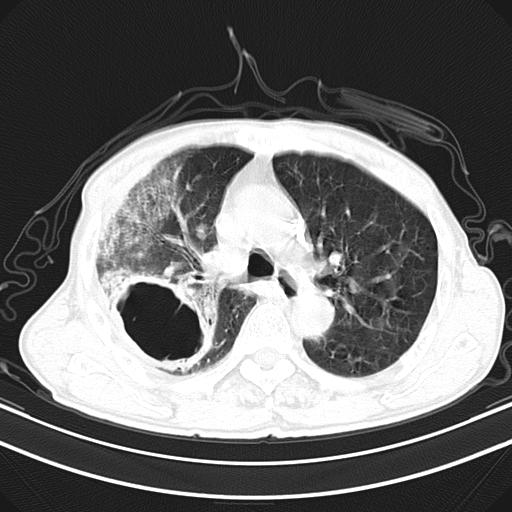

抗炎治疗10天后复查

抗炎治疗10天后复查:右上肺模糊阴影明显减少。

右肺感染性病变(右肺上叶肺脓肿?);建议:抗炎治疗后复查。